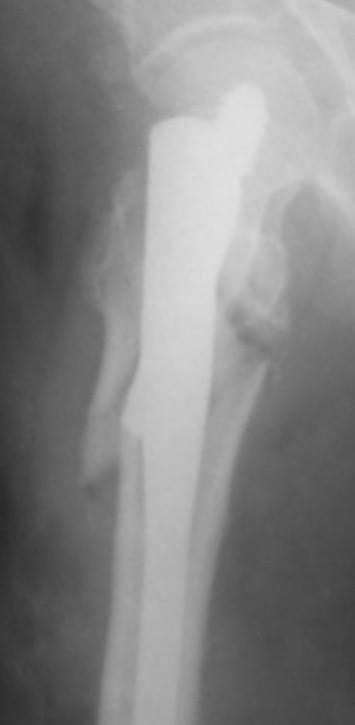

[Ortho] Осторожно! НПП "Имплант", г . Казань

Как-то так